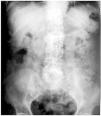

Mujer de 62 años en hemodiálsis crónica desde hace 6 años, con Diabetes Mellitus, hiperparatiroidismo secundario e hipertensión arterial como antecedentes personales más importantes. Consulta por sensación de plenitud abdominal, estreñimiento y nauseas. La exploración física y resultados analíticos fueron irrelevantes, destacando en la radiografía simple de abdomen material radio-opaco, disperso por todo el recorrido del colon, recordando una imagen de cielo estrellado. Revisando el tratamiento, se observó que desde hacía cuatro meses estaba tomando Carbonato de Lantano. Inicialmente asociado a otros quelantes del fósforo. La paciente no había recibido ningún tipo de contraste en los últimos 6 meses. Tras la retirada del Carbonato de Lantano y tratamiento con laxantes, la sintomatología desapareció y en la radiografía de abdomen realizada 3 semanas después apenas se apreciaba material radio-opaco.

Figura 2. Radiografía de abdomen en vacío a continuación del tratamiento